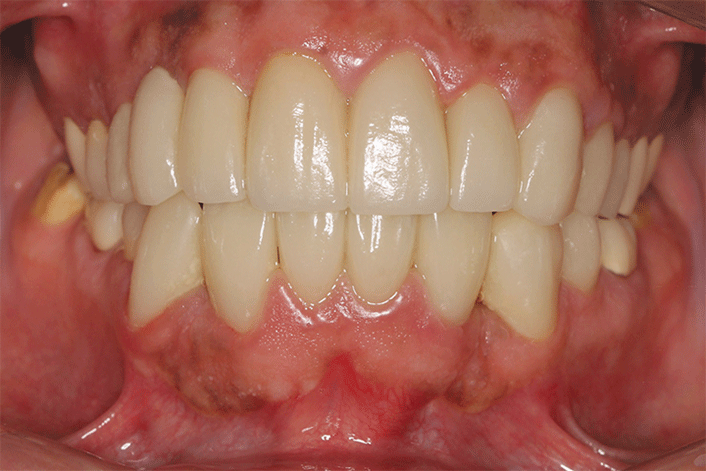

Now online in the Journal of Prosthodontics, Drs. Liliana Ortiz, Ann Marie Pereira, Leila Jahangiri, and Mijin Choi present a clinical report of a 16-year-old male patient with amelogenesis imperfecta (AI).

Adolescent patients require prosthodontic treatment design that can be adapted to the changes in arch shapes, sizes, interarch relationship, and esthetic needs, and this report discusses treatment recommendations, timing of various treatment modalities, and involvement of appropriate interdisciplinary teams for managing adolescent patients.